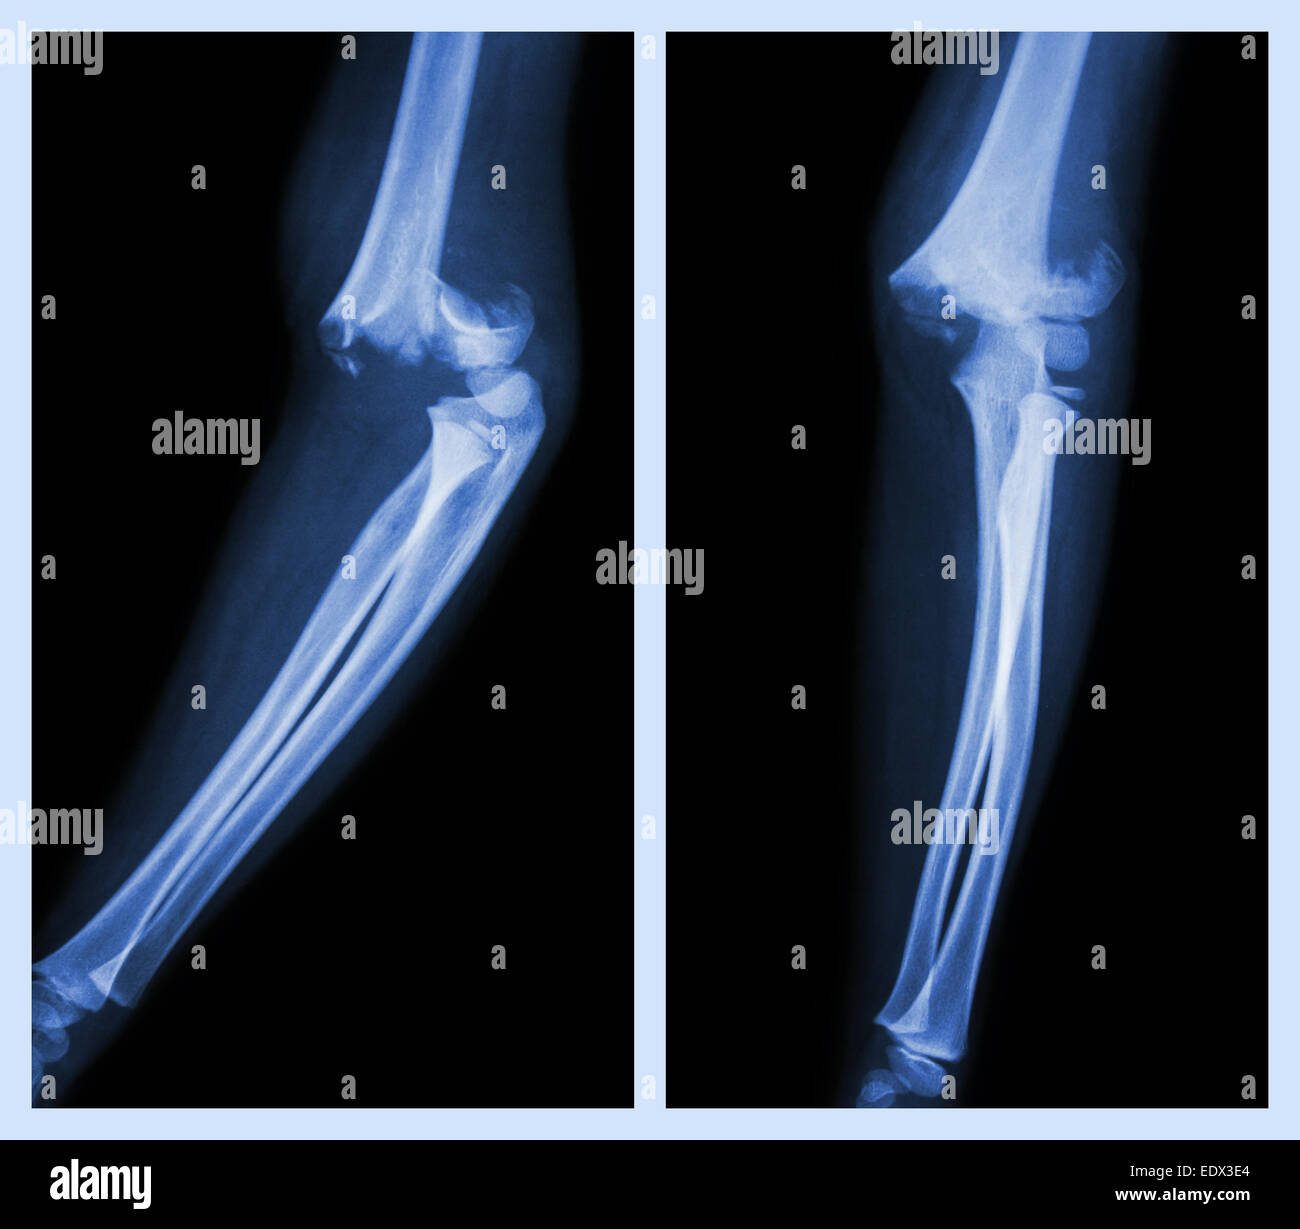

From www.alamy.com

Fracture elbow (Left image side position , Right image front Types Of Elbow Fracture Type i and ii fractures are usually treated without surgery, while type iii fractures typically need surgery. Elbow (radial head) or neck fracture. Depending on the severity of the injury, nonsurgical and surgical options exist to help repair the broken bone. You’ll also have injured some of the soft tissues around it. Sometimes, this bruising travels up the arm toward. Types Of Elbow Fracture.